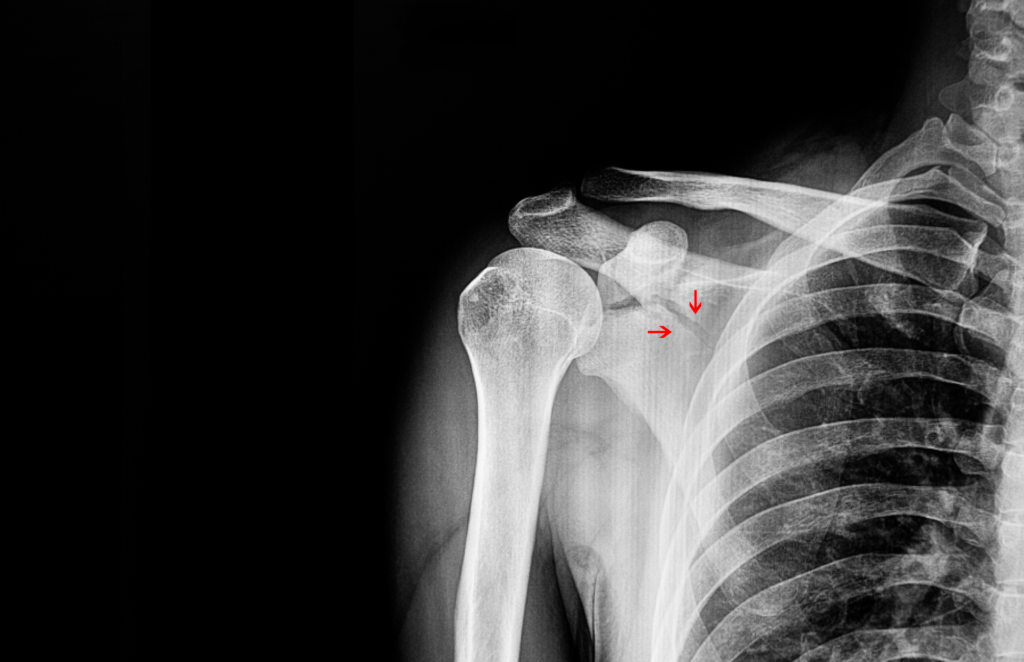

Diagnosi

La diagnosi delle lesioni del sottoscapolare si basa su un esame clinico approfondito, che include la valutazione dei sintomi del paziente, come dolore, debolezza e limitazione del movimento della spalla. Test specifici, come il test di Gerber o il test del “Lift-Off”, possono aiutare a identificare una lesione del sottoscapolare. L’imaging, come l’ecografia o la risonanza magnetica (RM), può confermare la diagnosi e valutare l’entità della lesione.